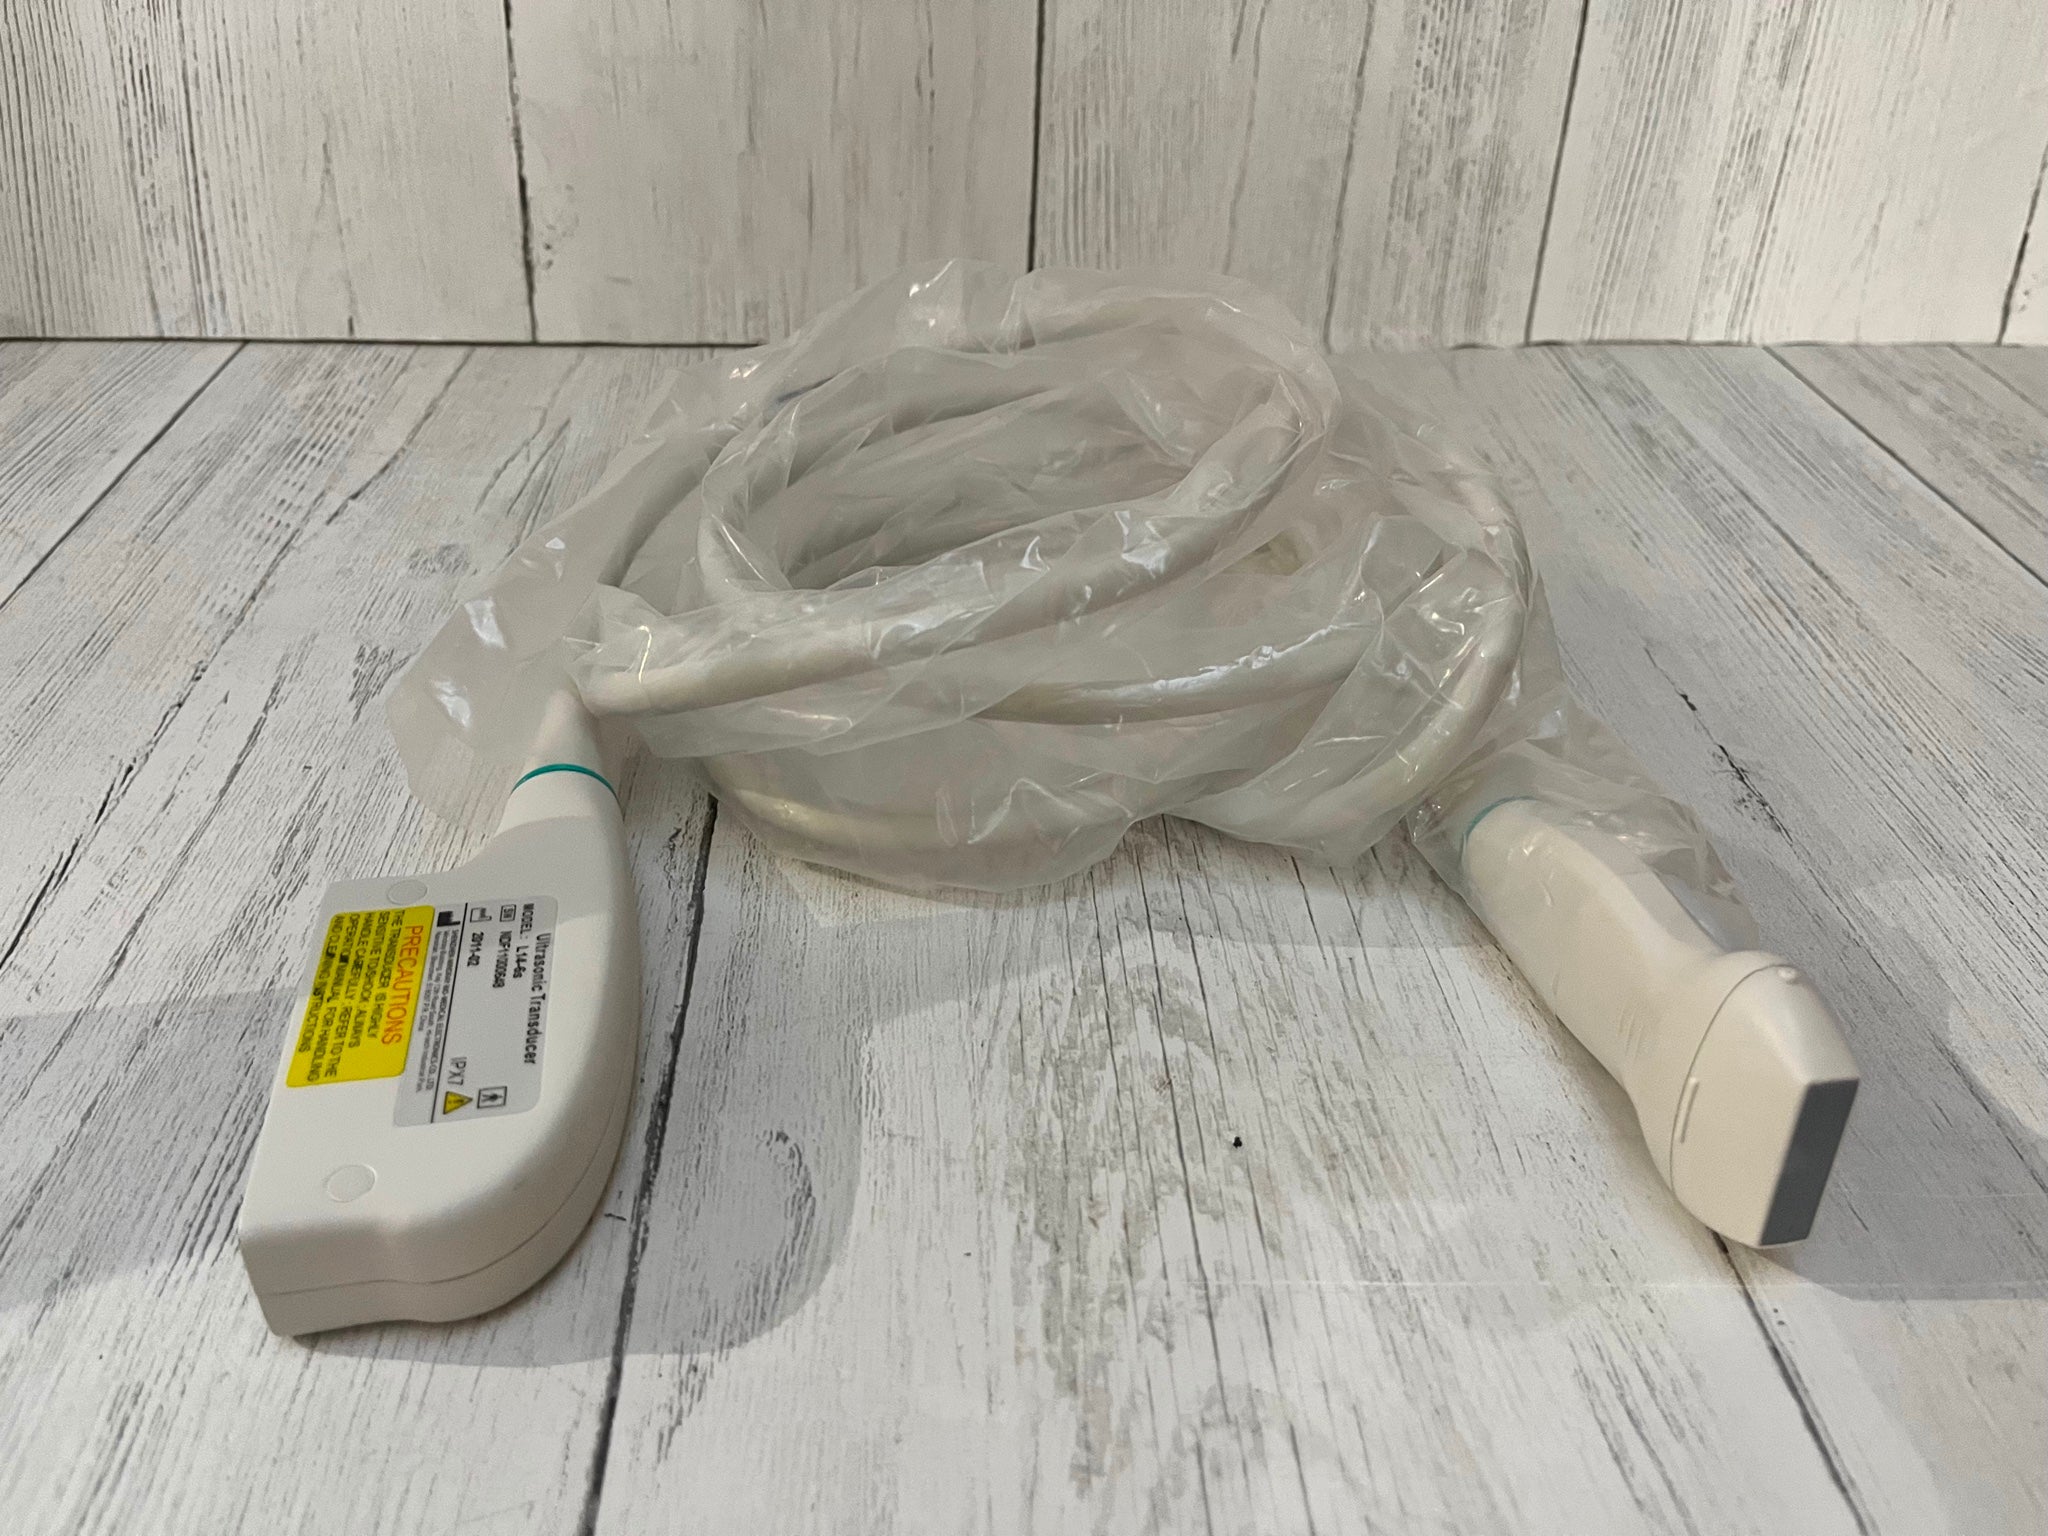

SAMSUNG HM70A PORTABLE ULTRASOUND WITH 2 PROBES

Sale price$ 11,150.88